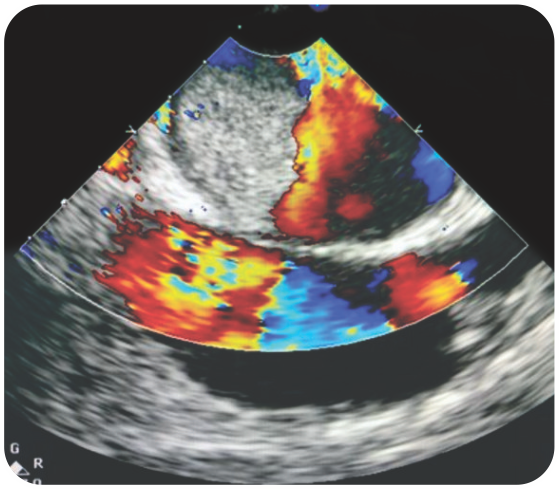

Case 5 - Left Atrial Myxoma with Heart Failure